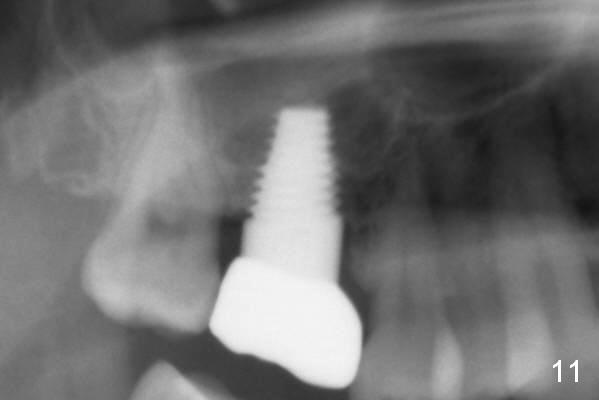

The tooth #3 of a 45-year-old man has endo failure (Fig.1), which shows that the sinus floor (^) is lower than the root tips. Fig.2 is taken a few days post extraction. Note low bone density in the socket, which is the basis for bone condensation. Five months later the patient returns for implantation. A ~12 mm incision is place in the edentulous ridge. The osteotomy forms by using osteotomes (rounded tapered 2-4 mm), followed by insertion of a 4.5x14 mm tap at the depth of 11 mm (Fig.3). It appears that the tip of the tap is in the sinus, but the top of the osteotomy has solid bone when the tap is removed. The bone is being expanded until 7x14 mm tap at the depth of 11 mm (Fig.4). The roof of the osteotomy is still intact. It appears that bone expansion intentionally lifts the sinus floor.